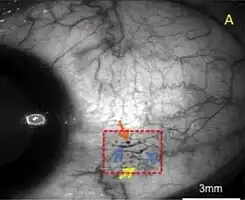

A case of conjunctival microangiopathy (red dashed-square) secondary to diabetes demonstrating a microaneurysm (orange arrow), vessel dilatation (blue arrows), and vascular tortuosity (yellow arrow).